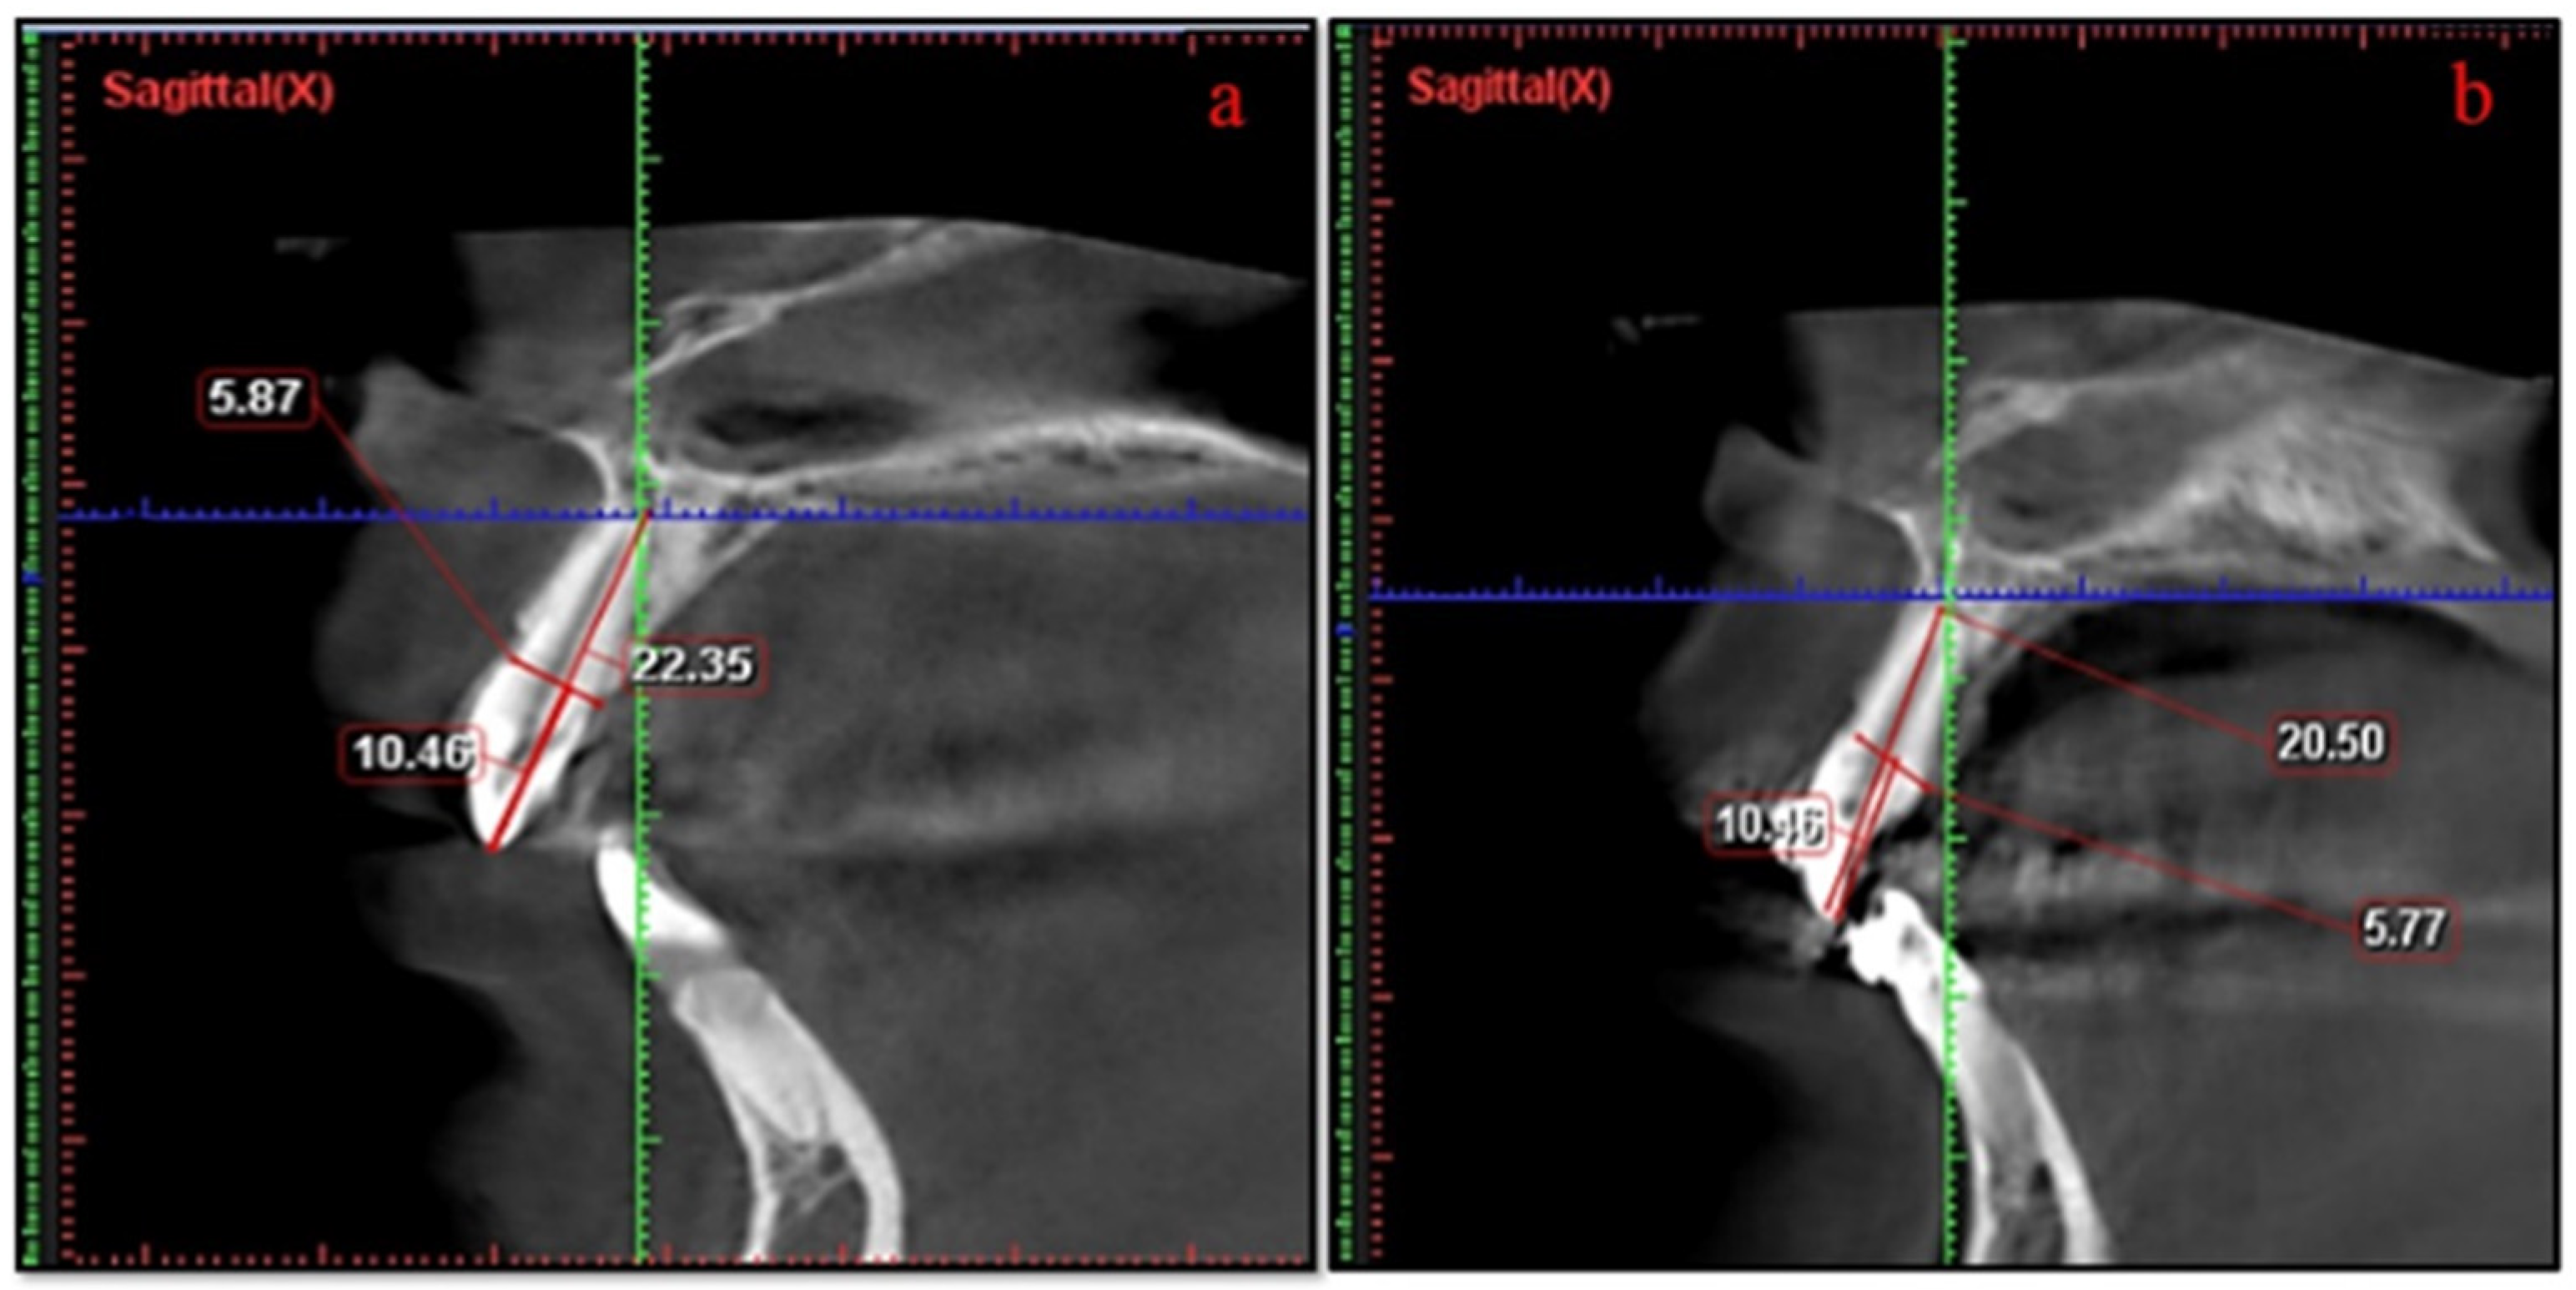

RR of the anterior teeth was evaluated via the CBCT images with Planmeca RomexisTM software 2.3.1.R (Helsinki, Finland). The tooth length of each anterior tooth was measured by dividing the tooth into two portions with cementoenamel junction (CEJ): crown (C) and root (R) (Figure 2). Apex to CEJ is considered as root length and CEJ to the tip of the cusp is considered as crown length. Crown length should remain consistent over the period of observation; therefore, a correction factor (CF) was calculated [15]. RR was measured from the CBCT images by using the following formula:

[R1 = root length measured at T1 stage (mm), R2 = root length measured at T2 stage (mm), C1 = crown length measured at T1 stage (mm), C2 = crown length measured at T2 stage (mm)] (Figure 3).

Figure 3. Measurements of root resorption (a) Sagittal view of CBCT showing the pre-measurement of root length (b) Sagittal of CBCT showing the post-measurement of root length.